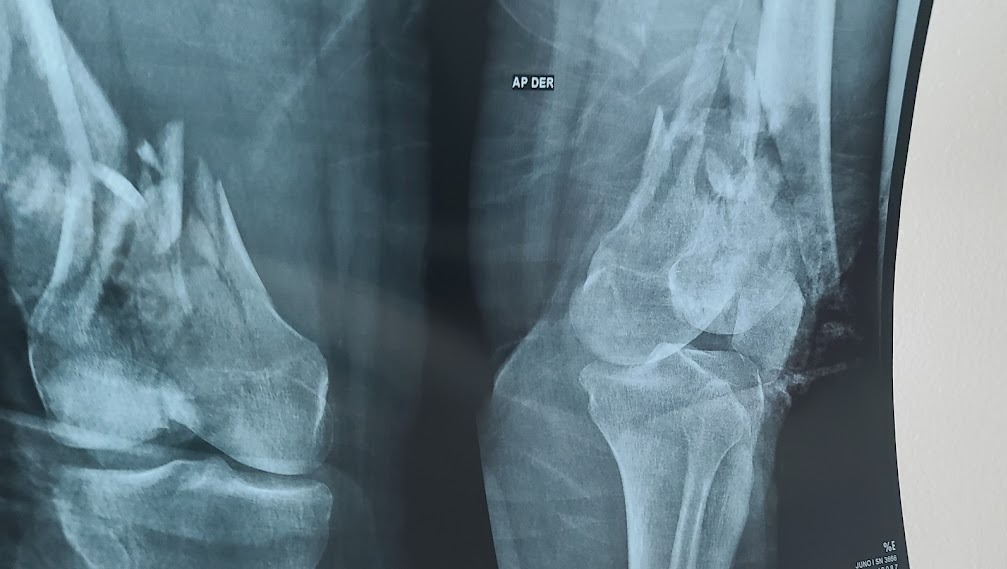

Below you will see some photos...they are tough to look at, but they show the true scope of the damage and what she is dealing with.

After getting injured an hour and a half into my dream vacation by breaking both my femurs, these past four weeks have been a very long, painful road and just the beginning of my healing journey.

Here doctors began the journey to get me stable and repair my legs. Unfortunately, my body started to now fight an invisible infection. During my 2nd surgery, they discovered a very dangerous Multi-Drug Resistant Organism infection in both my legs. Doctors began the process to clean my wounds. The left leg was swept and stable, but the right was far more infected, and quite a battle to get infection-free.

As of today, after undergoing nine surgeries and eight blood transfusions, the rod and screws are now installed on both my legs. I have begun my physical and occupational therapy to build my strength and prepare for the final surgeries.

I have made strides on my left side. However, my right side continues to become more and more painful each day. Unfortunately, a CT Scan and ultrasound discovered a mass of fluid in my right leg at the bottom of my femur under my knee. My team is determining if another surgery is needed to remove the liquid or a better course of treatment to correct; it before they release me to fly home to California for my six weeks of PT.

The big picture goal is mid-February I will be air flighted back to California to continue my physical therapy for six weeks; then, at the end of March, I will come back to Houston for the last phase. At that time, Dr will be installing the final plates to hold my bones together, all additional screws and rods. This last phase is vital to get my legs stable to provide strength and stability; so that eventually I will be able to walk again, which is, of course, the end plan.